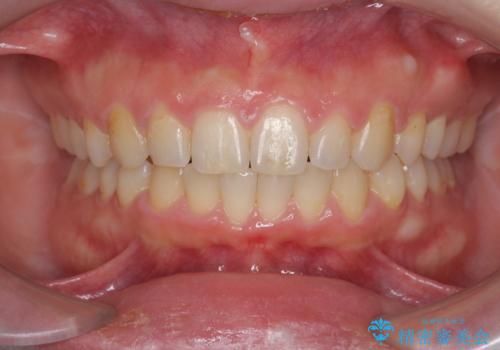

深い噛み合わせ、すきっ歯の改善 ワイヤーを用いたマルチブラケット矯正

ワイヤーを用いたマルチブラケット矯正を行うことで深い噛み合わせを改善し、前歯の隙間もなくし審美的な歯列へと治療をおこなっていきます。

深い噛み合わせの改善は前歯の圧下が必要なため、治療期間が長期化することが多いです。